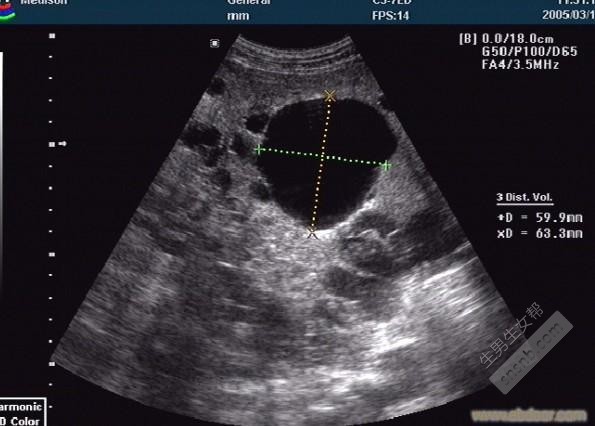

医生告诉我,我是多囊卵巢综合征。让我老公也来检查,他一开始不愿意来,后来在我再三恳求下检查了。结果没有一点问题,他嘲笑我,说我想把责任推给他,明明是我妈没给他一个好身体的闺女。我也一直觉得,是自己有问题,不能怪他骂我。

然后,我开始了三年的吃中药,吃西药,促排。循环,我们这边的医院,只要是生殖科的医生没有一个人不认识我的。因为我跑医院的次数,几乎是只有他们休息我才会不去。(所有的费用全是我自己负担,或者妈妈给我)医生要求我重新检查输卵管。因为我已经促排了8次了。